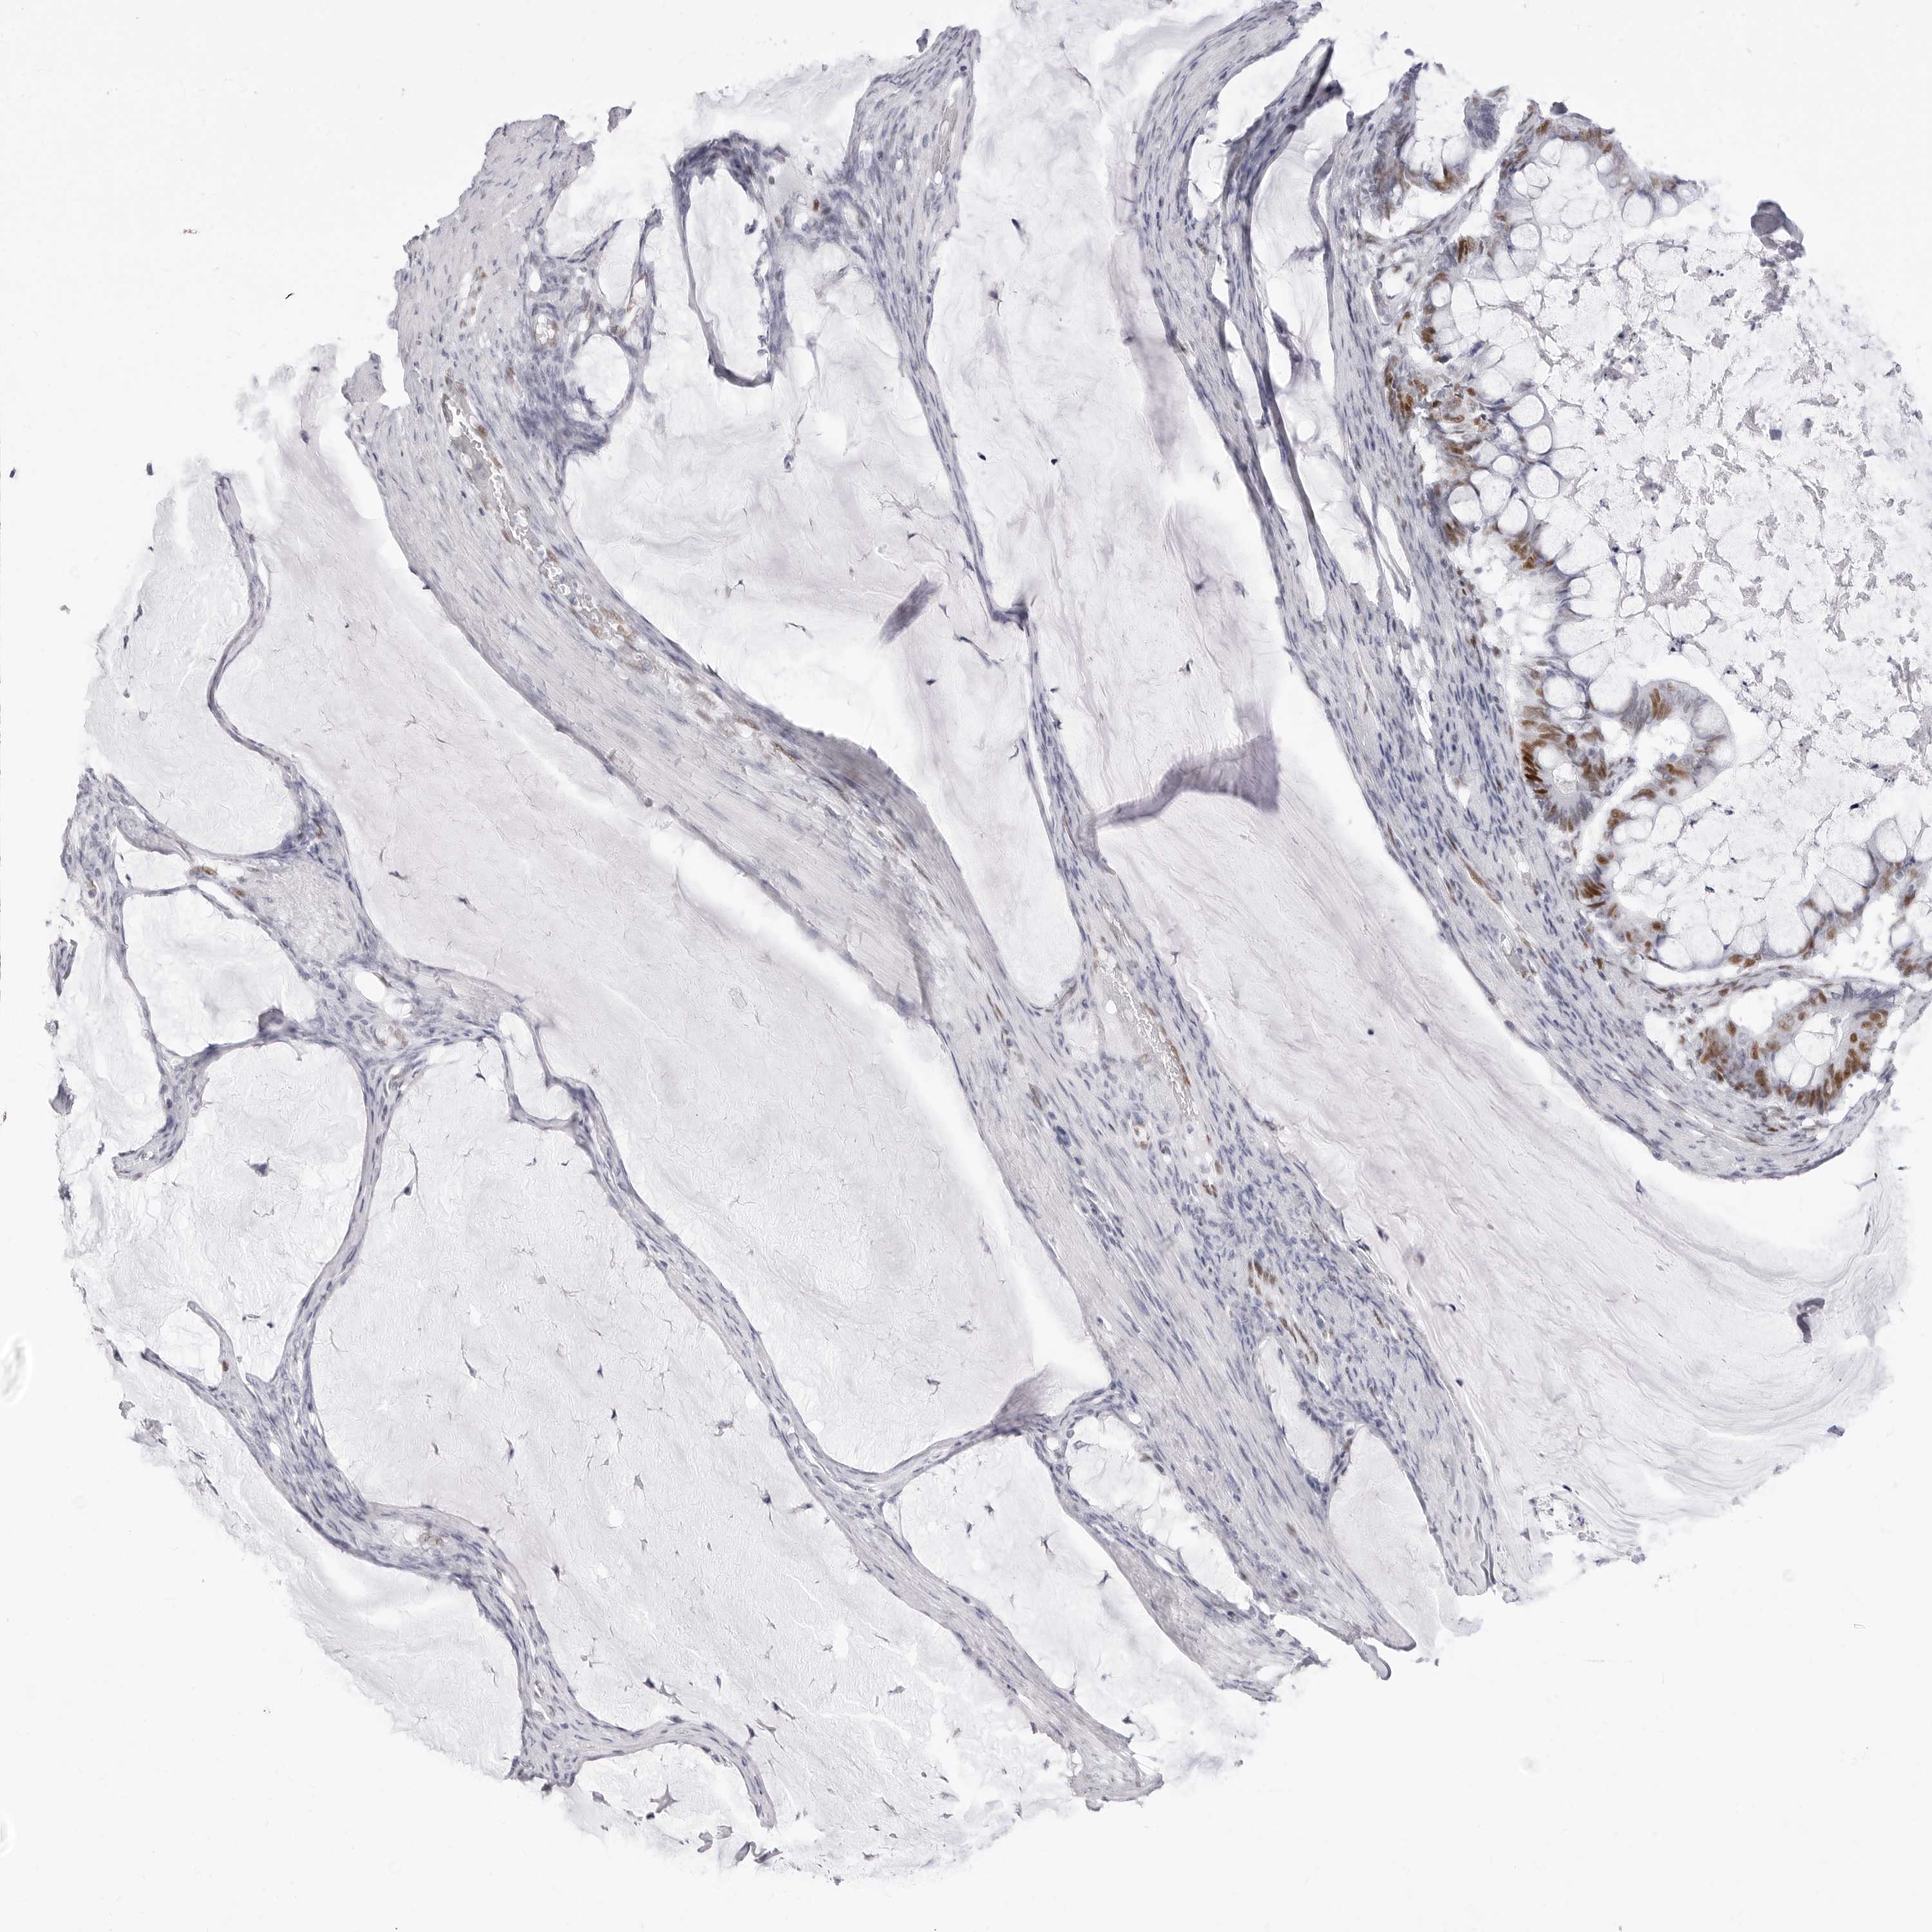

OVARIAN CANCER - Protein expressioni

A mouse-over function shows sample information and annotation data. Click on an image to view it in a full screen mode. Samples can be filtered based on level of antibody staining by selecting one or several of the following categories: high, medium, low and not detected. The assay and annotation is described here.

Note that samples used for immunohistochemistry by the Human Protein Atlas do not correspond to samples in the TCGA dataset.

Antibody stainingi

Antibody staining in the annotated cell types in the current human tissue is reported as not detected, low, medium, or high, based on conventional immunohistochemistry profiling in selected tissues. This score is based on the combination of the staining intensity and fraction of stained cells.

Each image is clickable and will lead to virtual microscopy that enables deeper exploration of all samples and also displays staining intensity scores, fraction scores and subcellular localization as well as patient and tissue information for each sample.

Antibody HPA028136

Antibody HPA030518

Antibody HPA030520

Staining

High

Medium

Low

Not detected

Cystadenocarcinoma, serous, NOS

Carcinoma, endometroid

Cystadenocarcinoma, mucinous, NOS

Carcinoma, NOS